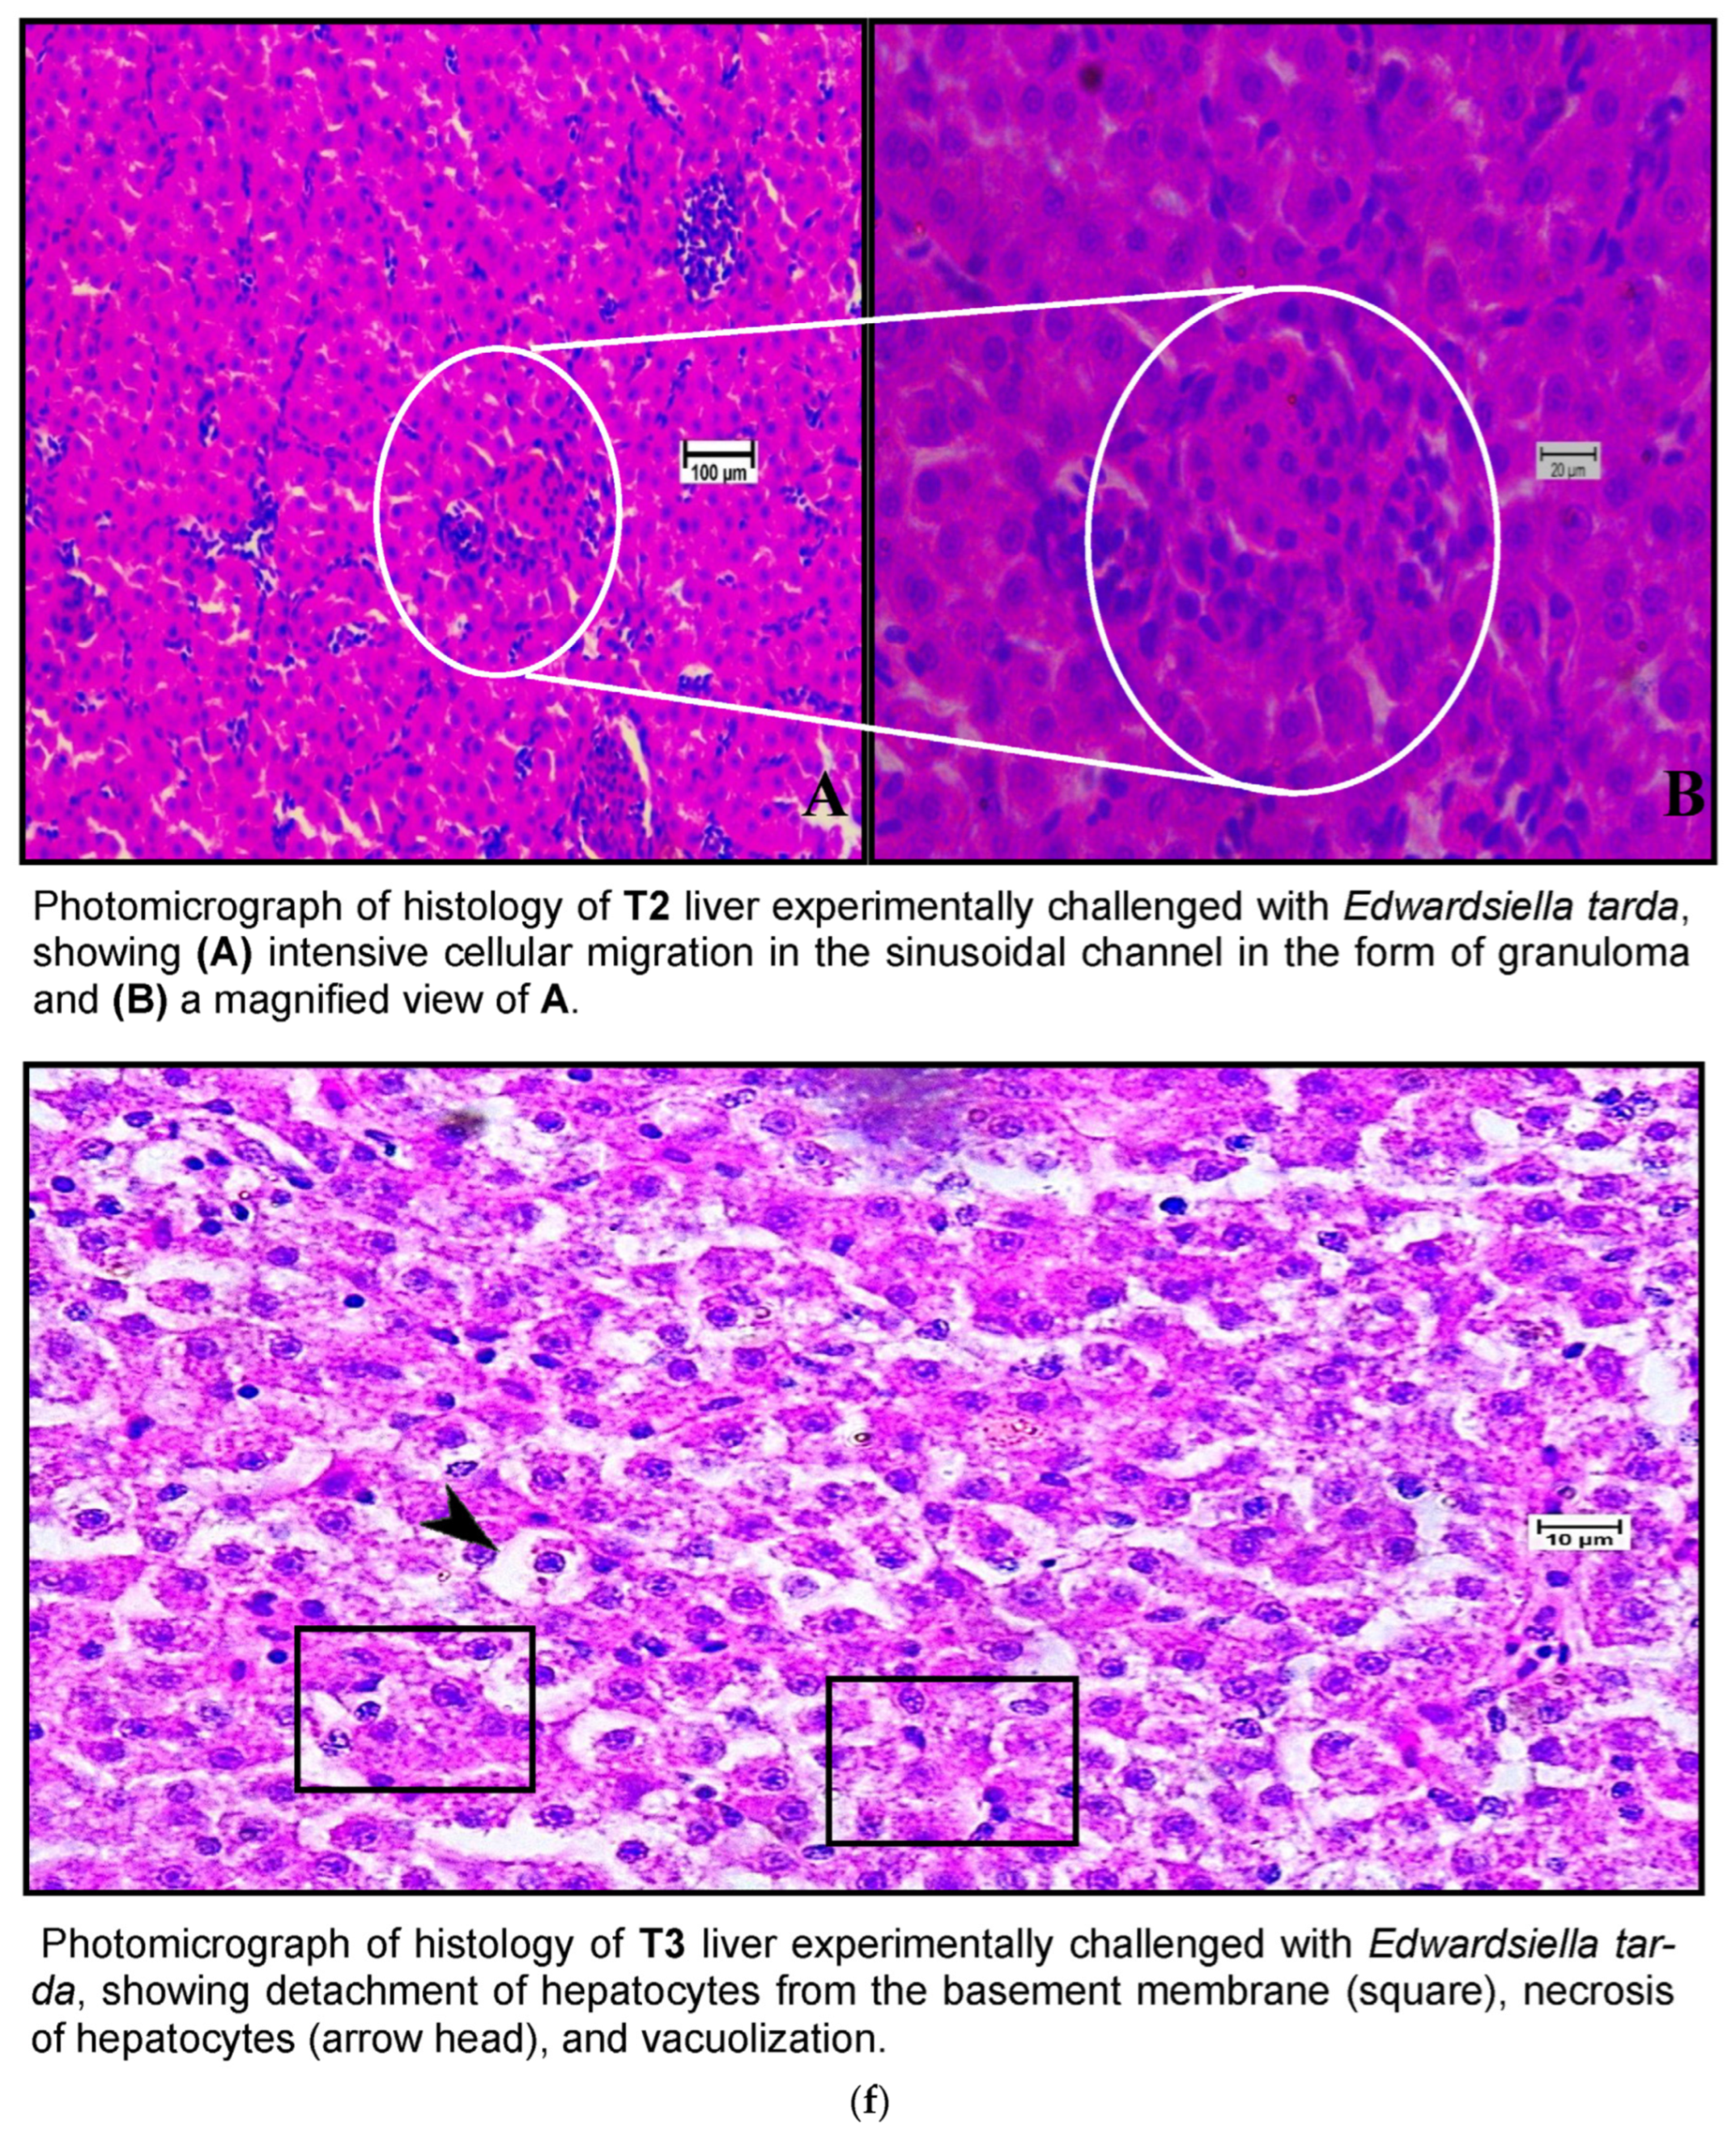

Figure 7.

(a) A photomicrograph of the livers of CT and T1 groups. (b) A photomicrograh of the livers of T2 and T3. (c) A photomicrograph of the livers of CT and T1 groups challenged with A. hydrophila. (d) A photomicrograph of the livers of T2 and T3 groups challenged with A. hydrophila. (e) A photomicrograph of the livers of CT and T1 infected with E. tarda. (f) A photomicrograph of the histology of the liver of T2 and T3 infected with E. tarda.

Histological examination of the livers of fish fed the control diet (CT) and the high-dose TABP diet (T3) revealed significant differences in the liver pathology (Figure 7a,b). The livers of fish fed the CT diet had a normal organization of polygonal hepatocytes, normal bile duct, and central vein. In contrast, the livers of fish fed the T3 diet showed fibrosis with fat deposits and altered the normal architecture of the hepatocytes. These findings are consistent with previous studies that have shown that high doses of TABP can cause liver damage in fish. The liver is a vital organ for fish, as it plays a role in digestion, absorption, metabolism, and detoxification. Liver damage can lead to a number of problems, including impaired growth, decreased reproduction, and increased susceptibility to disease. The findings of this study suggest that high doses of TABP can cause liver damage in fish, and further research is needed to determine the safe level of exposure for fish. In addition to the histological changes, the fish fed the T3 diet also had increased levels of oxidative stress markers in the liver. Oxidative stress is a condition that occurs when there is an imbalance between the production of free radicals and the body’s ability to remove them. Free radicals are unstable molecules that can damage cells and tissues. The increased levels of oxidative stress markers in the fish fed the T3 diet suggest that TABP may be causing oxidative stress in the liver, which could contribute to the liver damage observed in this study. The findings of this study provide evidence that high doses of TABP can cause liver damage in fish. Further research is needed to determine the safe level of exposure for fish and to identify the mechanisms by which TABP causes liver damage.